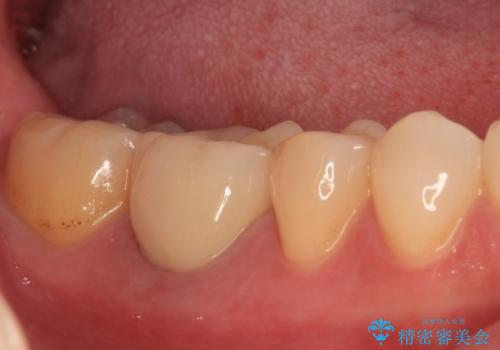

腫れていた歯茎は根管治療後に解消され、適合の良いセラミッククラウンを装着することができました。